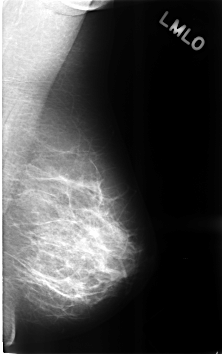

C_0306_1.LEFT_MLO

LEFT_MLO LINES 4600 PIXELS_PER_LINE 2880 BITS_PER_PIXEL 12 RESOLUTION 50 NON_OVERLAY